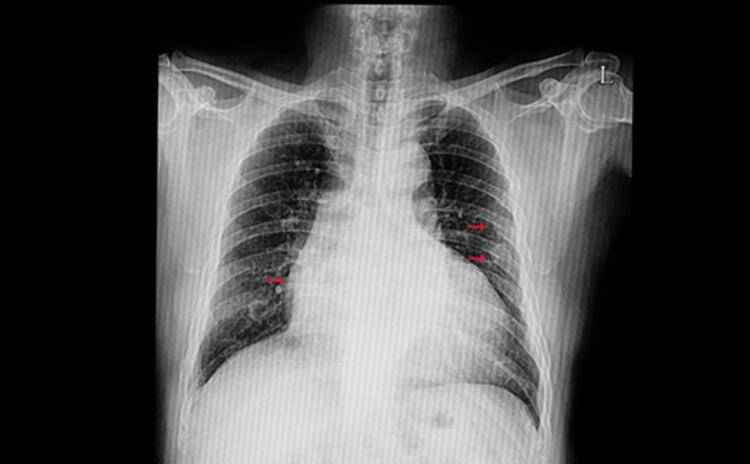

- Akciğer kanseri, gelişmiş tedavi süreçlerine rağmen en ölümcül kanser türü olmaya devam ediyor. Cancer.org şöyle açıklıyor: “Akciğer kanseri, kanser ölümlerinin açık ara önde gelen nedenidir ve tüm kanser ölümlerinin neredeyse yüzde 25’ini oluşturur. Her yıl, kolon, meme ve prostat kanserlerinin toplamından daha fazla insan akciğer kanserinden hayatını kaybediyor.”

- Akciğerler bir iç organ olduğundan, dışarıdan incelenemezler ve Ulusal Kanser Araştırmaları Vakfı’na göre semptomlar ancak kanser ilerlediğinde ortaya çıkar.

- AKCİĞER KANSERİNİN TEŞHİSİ ÇOK ZOR… Akciğer kanserinin teşhisi zor olduğundan ötürü vakalar çok geç tespit edilir. Hastalığın belirtileri ortaya çıkmaya başladığında, bazen içinde kan bulunan mukusun eşlik ettiği kronik, hırıltı, hırıltılı bir öksürük içerebilir.

- AKCİĞER KANSERİNİN BELİRTİLERİ… Akciğer kanserlerinin en sık görülen belirtileri şunlardır; Geçmeyen veya giderek kötüleşen öksürük. Öksürürken kan veya kanlı balgam çıkarmak Derin nefes alırken, öksürürken veya gülerken kötüleşen göğüs ağrısı, iştahsızlık, halsizlik, yorgunluk, kilo kaybı, ses kısıklığı, nefes darlığı, sürekli tekrarlayan veya geçmeyen bronşit veya zatürre gibi akciğer enfeksiyonları. (Posta)